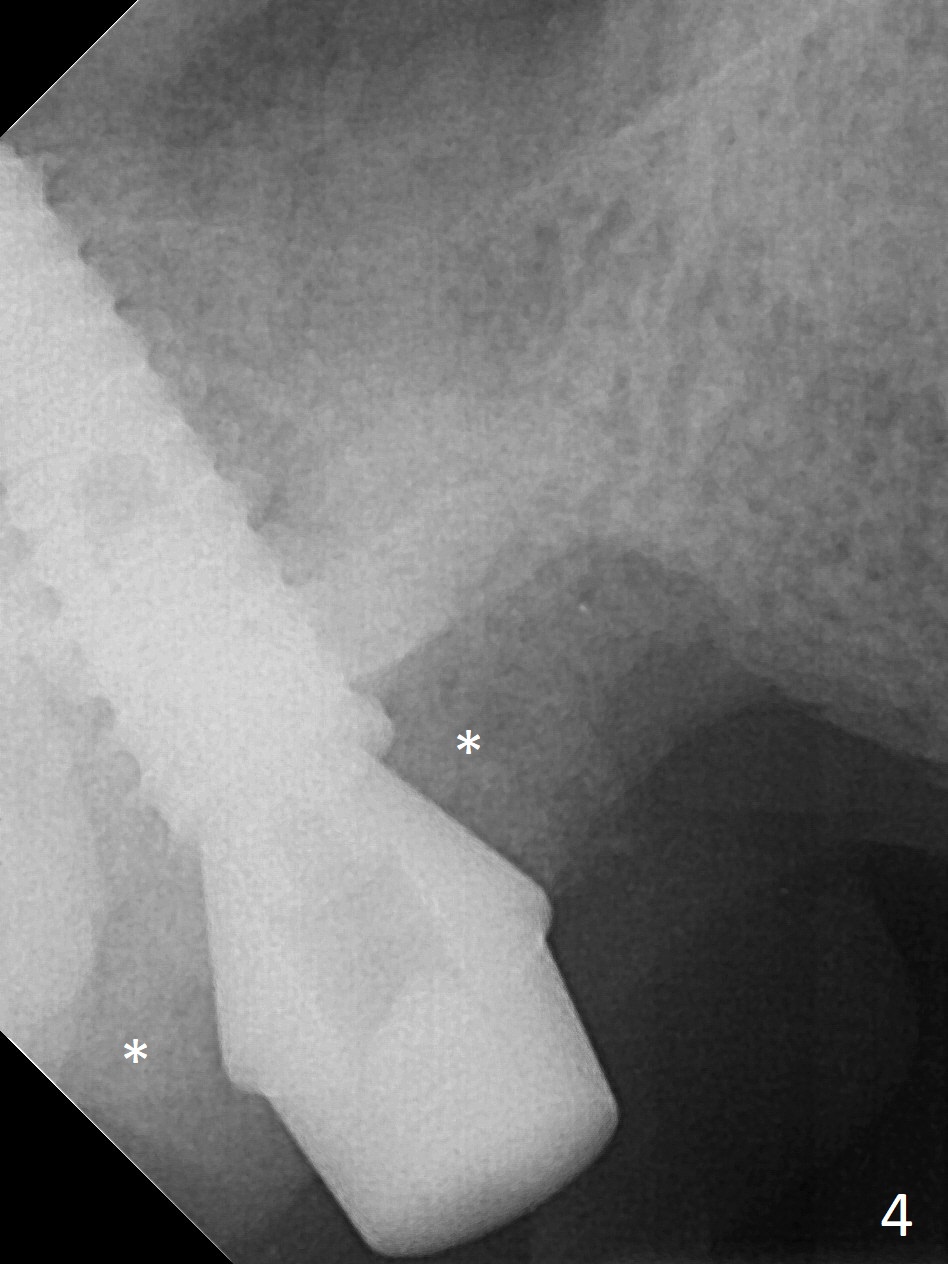

It is difficult to use hard tissue landmark (drill stopper) to make osteotomy in the fresh extraction socket because of socket irregularity and hemorrhage. Once osteotomy is initiated, depth is more reliably controlled with soft tissue landmark (such as gingival margin). This happens in today's case. Without CT information, the osteotomy is established in the buccal slope of the septum of the tooth #2 (after extraction) by using alternatively Magic Sinus Lifter and 4.8 mm Magic Drill (MD). Finally the sinus floor (Fig.1 red dashed line) is lifted after the MD reaches ~16 mm counting from the gingival margin, consistent with preop panoramic X-ray and intraop PA measurement. The 4.5x11 mm dummy implant is close to the impacted 3rd molar (1). Following use of Lindamann bur to move the osteotomy mesially, a 5x9 mm dummy implant is placed away from the 3rd molar (Fig.2 (3: residual root of the 1st molar)). The latter is intentionally not removed in order to maintain osteotomy integrity. A 5x13 mm IBS implant is placed with >50 Ncm; a 6.5x4(4) mm abutment is hand tightened (Fig.3). The remaining large socket is filled with Vera Graft (Fig.4 *). Two months postop, the abutment changes to 6.5x5.7(2) mm without provisional (Fig.5). Nearly 3 months postop, the patient will return for #3 residual root extraction and implant placement with incision (Fig.6). Osteotomy will be initiated in a slope. Prepare surgical round bur for flattening. After placement of a healing abutment, periodontal dressing is to be applied. Take photos to show gingival adaptation to the new abutment without implant exposure at #2.